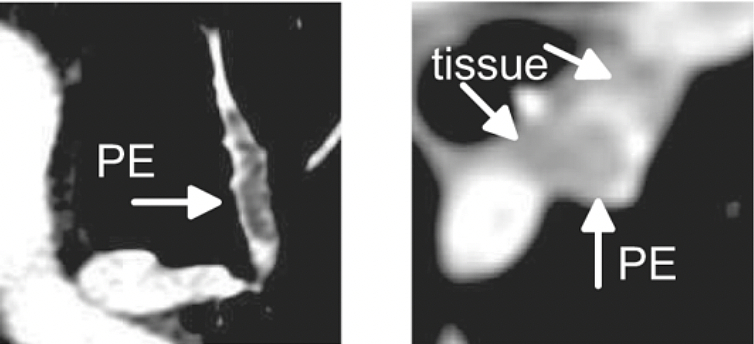

(a) In CT images, PE appears as a dark region inside the pulmonary arteries. (b) Lymphoid tissue and PE can have the same intensity.